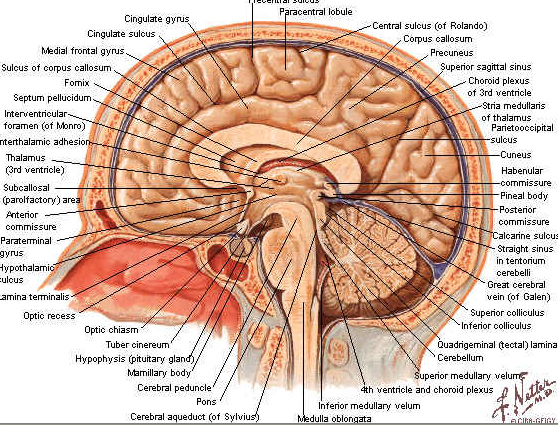

SISTEMUL NERVOS

SISTEMUL NERVOS Sistemul nervos stabileste legatura dintre organe, precum si dintre organism si mediul inconjurator, asigurand functionarea normala a intregului organism. Dupa funcţCiteste tot ... 1883 cuvinte

Dimensiune medie

+ cu poze |